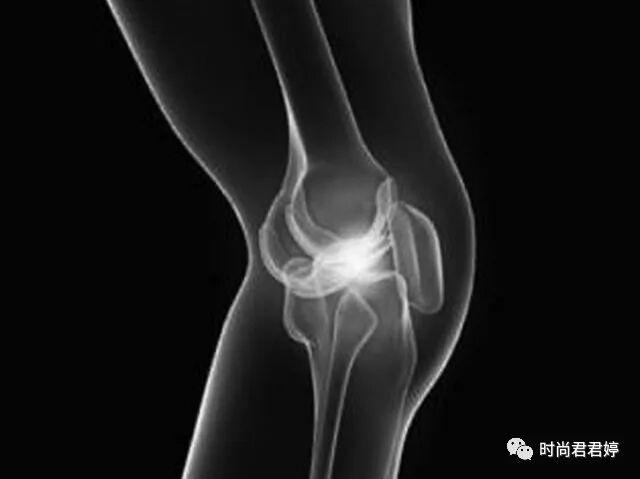

滑膜细胞分泌液体,可以润滑和滋养关节,机体运动时膝关节所产生的热能全赖于滑膜液体及其血液循环而得以散发。当关节受外在性和内在性因素影响时,滑膜发生反应,引起充血或水肿,并且渗出液体,表现为关节肿胀,痛疼,功能受障碍。也可说关节腔有积液,就有滑膜炎症。

其实,膝关节滑膜炎是老年人比较常见的一种病,多因生理性老化导致,表现为关节软骨营养不良,代谢异常,并出现骨刺。这种情况下,如果常被揉,只可能使软骨或骨刺剥脱,成为关节游离体,卡住关节,影响活动。此外,对于肿胀的关节,常揉后还会刺激发炎的滑膜,加重关节积液。因此,一旦发现关节僵直、变形,或者出现肿胀,就要想到可能是患上膝关节滑膜炎了,千万不要经常揉。